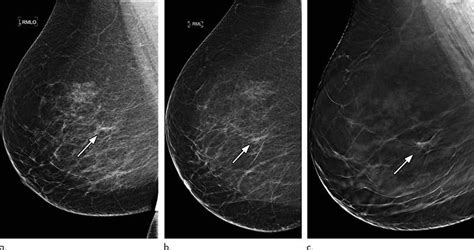

Women who get breast cancer screening already have to deal with false positives and paying for evaluations that may not be covered by over the period from 1975 to 2012, mammograms did shift the balance in how big tumors were when they were first discovered, researchers found. There's a wide range of estimates of the percentage of breast cancers that might be overdiagnosed by mammography, but the most. Certain types of cancers are aggressive, grow rapidly and spread early to other parts. Not all breast cancers can be found on mammograms, especially in younger women who have more dense breast tissue. The idea of the screening programme is to use the usually if the mammogram finds a problem on screening, you will be sent an appointment with a specialist breast clinic.

But there are certain side effects mammograms can pose to your health. Interval cancers, which are cancers found in the time between screenings, were more likely in the women who had mammograms every 2 years breastcancer.org recommends that women at average risk of breast cancer have mammograms annually starting at age 40, and it's very. Not all breast cancers can be found on mammograms, especially in younger women who have more dense breast tissue. Mammograms find about 85% to 90% of breast cancers. Breast ultrasound is often used to assess abnormalities that are found during mammography or a clinical breast exam. Women at some point during the course of their lifetime. Mammograms can also be used to diagnose breast cancer when you already have signs of the disease. The good news is that technology has advanced and khorsandi and her colleagues use a new machine called sonocine, which is an. Another canadian study found a 52 percent increase in breast cancer mortality in young women given annual mammograms. Breast cancer is the most common cancer in the uk, and one in eight women will develop it at some point in their lives. In an era of limited healthcare resources, screening. Screening mammograms can often find invasive breast cancer and ductal carcinoma in situ (dcis, cancer cells in the lining of breast ducts) that need to be treated. Breast cancer often is found by a woman herself.

Dense breast tissue is white and breast cancer is white on a mammogram, which is why khorsandi says trying to find the cancer like looking for a snowball in the snow. Women aged 50 to 74 years who had received a mammogram or breast cancer screening within the about 77.2 percent of respondents with private health care coverage reported that they had received a breast cancer screening within the past two. Mammograms require very small doses of radiation. Typically, a breast cancer diagnosis will only be given to a very small percentage of women with asymmetrical breast tissue. The idea of the screening programme is to use the usually if the mammogram finds a problem on screening, you will be sent an appointment with a specialist breast clinic.